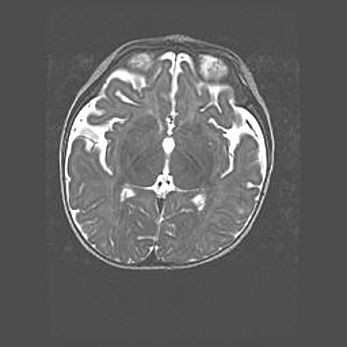

Открытая гидроцефалия.

Возраст: 9 месяцев 12 дней

Вес: 6800 г

Пол: мужской

Окружность головы: 41,5 см

Срок гестации: 28 недель

Гидроцефалия головного мозга у новорожденных имеет характерный признак: опережающий рост окружности головы приводит к визуально хорошо определяемой гидроцефальной форме сильно увеличенного в объёме черепа. Детские неврологи определяют следующие симптомы гидроцефалии у грудничков: выбухающий напряжённый родничок, частое запрокидывание головы, смещение глазных яблок к низу.